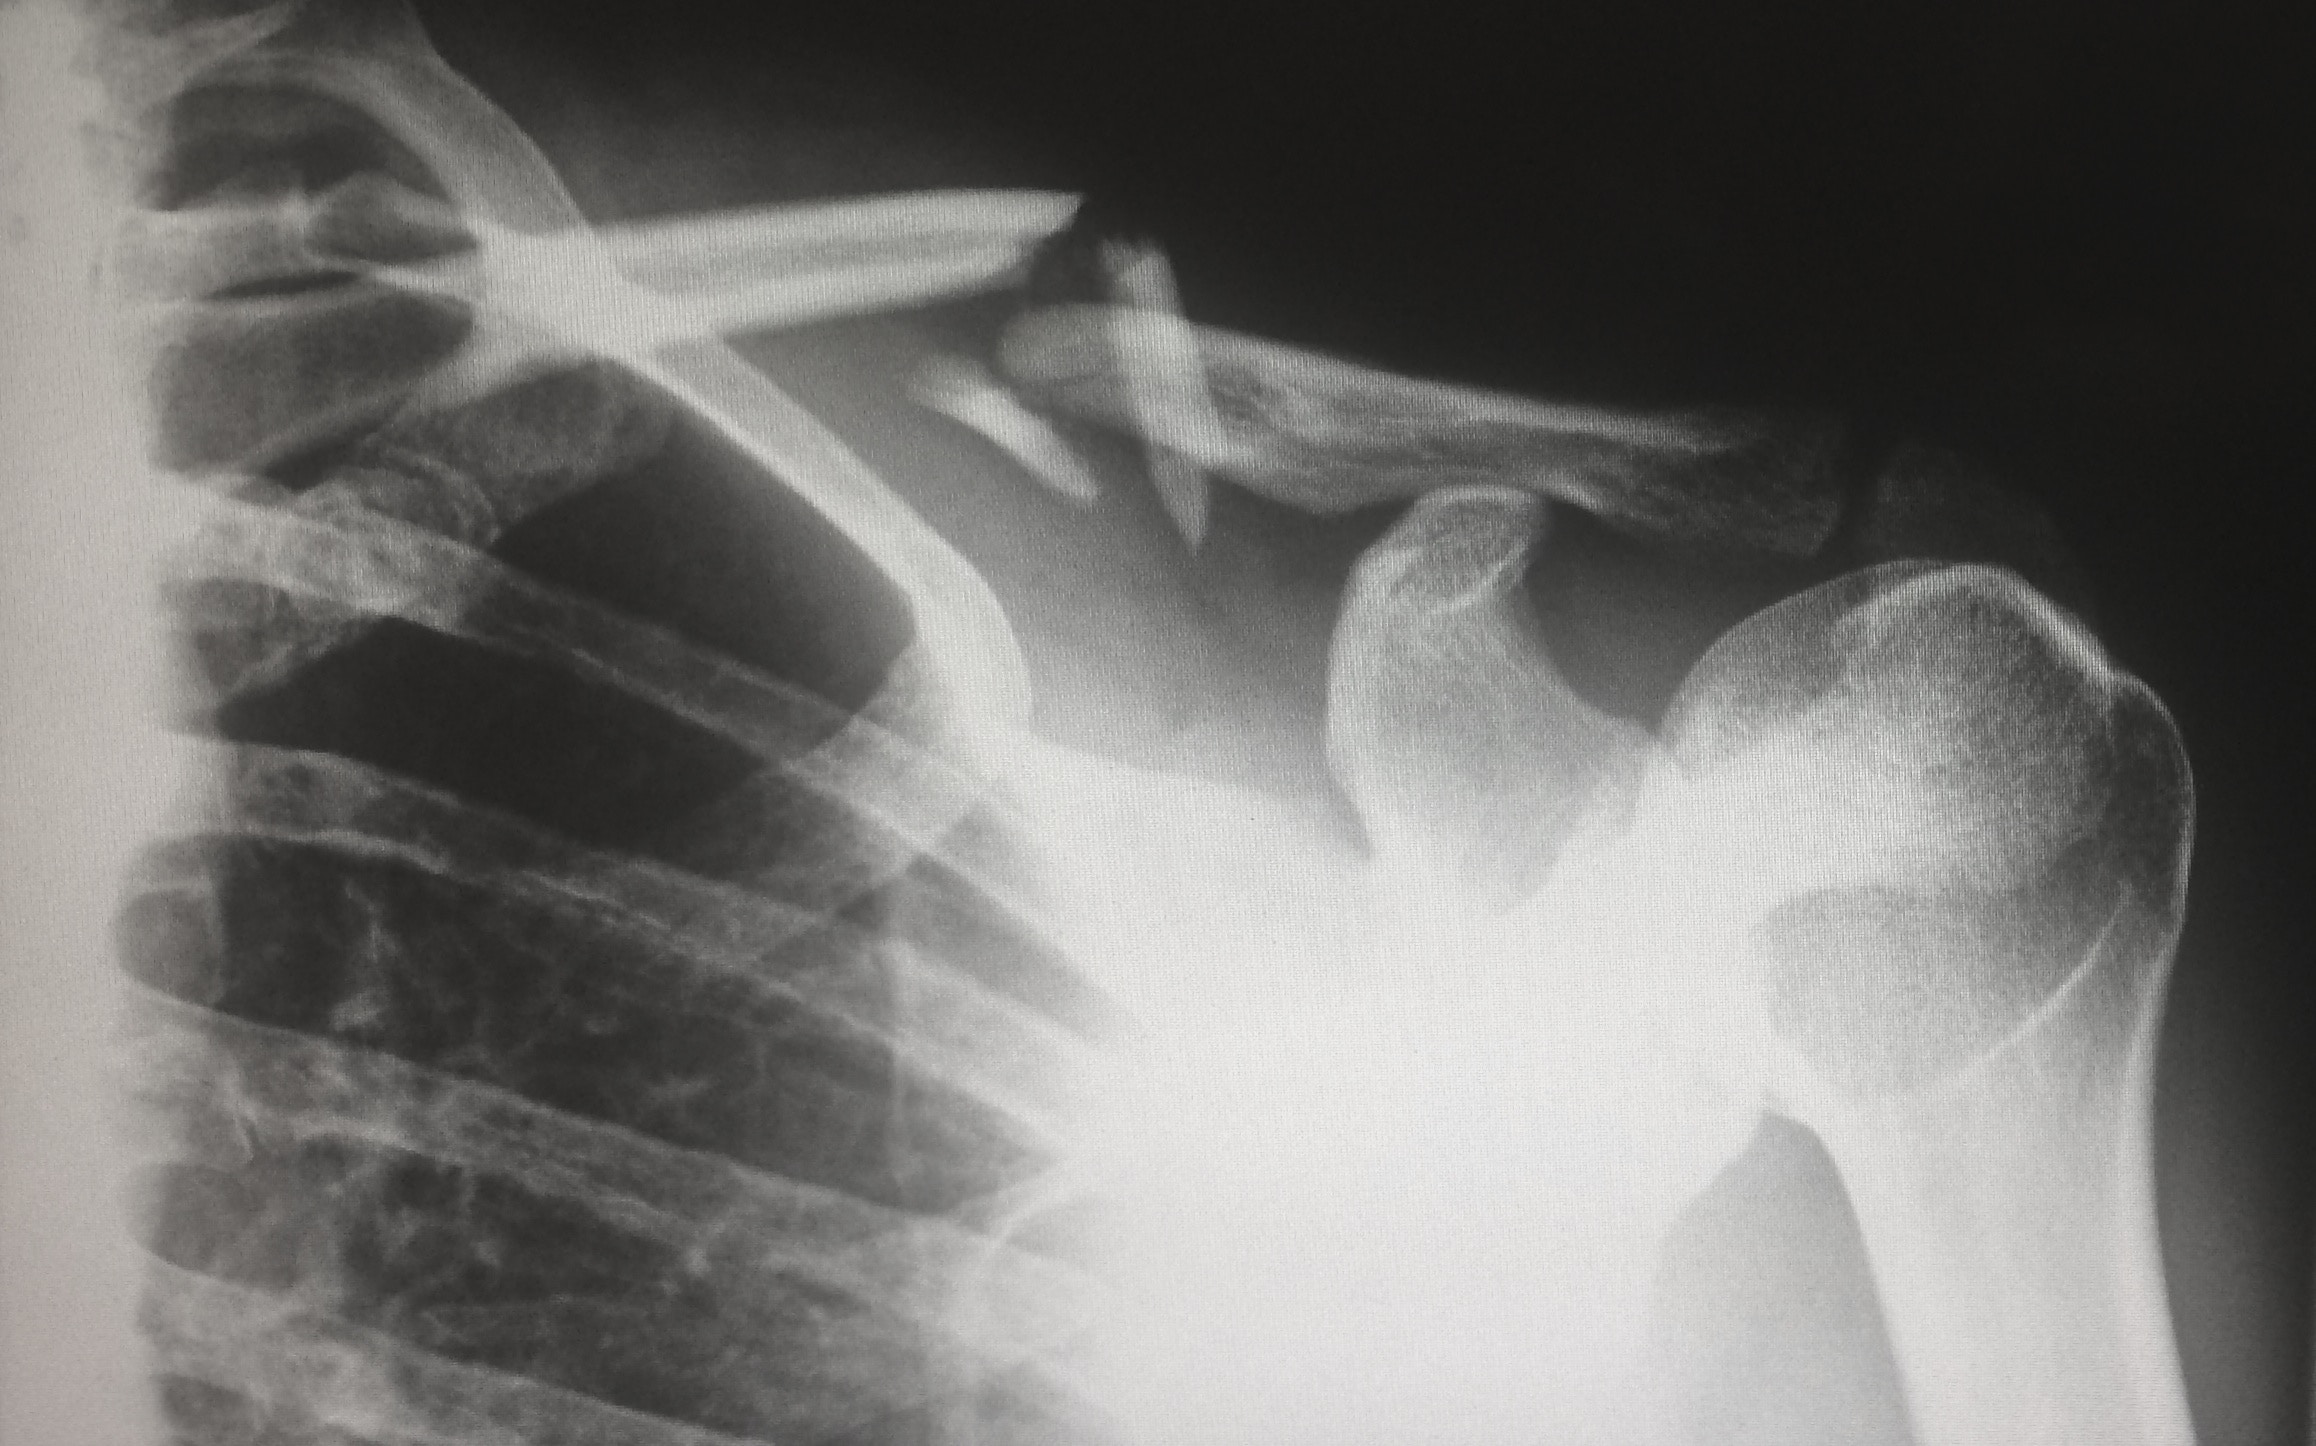

You should seek the services of a physio or sports doctor as soon as possible to get the best chance at a full recovery. An in-depth and accurate analysis of your issue is vital to come up with the best course of action for yourself. Imaging such as X-ray & MRI scanning could be necessary to be able to get you as much help as you need, which is another reason any scans need to be done ASAP.